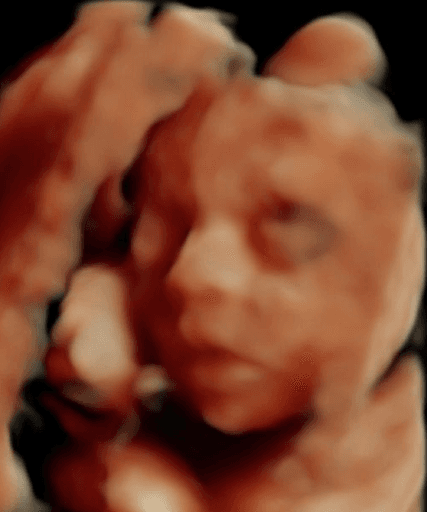

See babies, before & after

See your baby smile in 2 minutes.

Your 3D ultrasounds stay private. Images here are shown with permission — yours will never appear on this page without your consent.